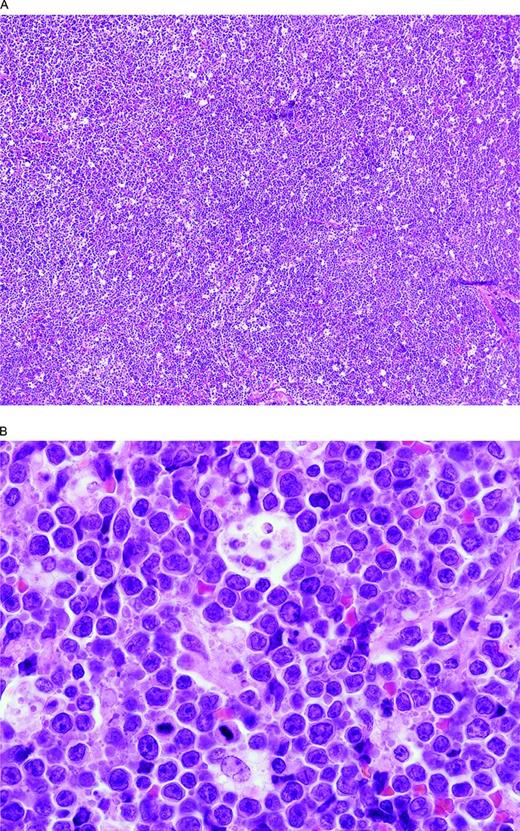

BCLU with MYC and BCL6 double-hit. (A) There is a diffuse proliferation with a starry sky pattern due to tingible body macrophages like in a BL. (B) At high magnification, note the rather monotonous proliferation of intermediate-size transformed cells and scattered tingible body macrophages. Although resembling a BL, there are more cells with single central nucleoli than would be typical and some irregular nuclear contours. The Ki-67 stain was extremely high but, unlike BL, the cells were CD10 negative and BCL2 positive (not illustrated).